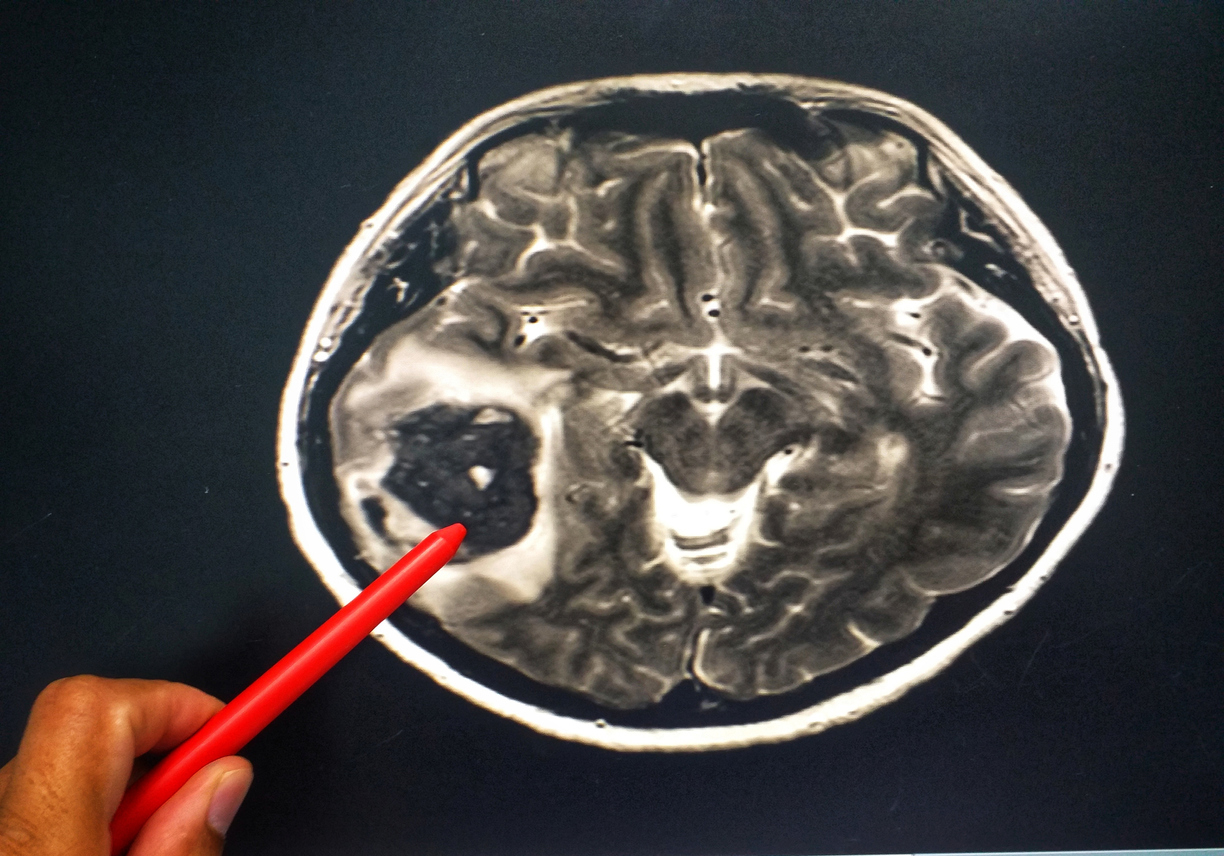

Într-un studiu considerat revoluționar, cercetătorii de la universitatea din Tel Aviv au eliminat în mod eficient glioblastomul, un tip extrem de letal de cancer cerebral.

„Glioblastomul este un cancer cerebral extrem de agresiv și invaziv, pentru care nu există niciun tratament eficient cunoscut. Celulele tumorale sunt foarte rezistente la toate terapiile cunoscute și, din păcate, speranța de viață a pacientului nu a crescut semnificativ în ultimii 50 de ani. Descoperirile noastre oferă o bază promițătoare pentru dezvoltarea unor medicamente eficiente pentru tratarea glioblastomului și a altor tipuri de tumori cerebrale”, au scris autorii studiului.